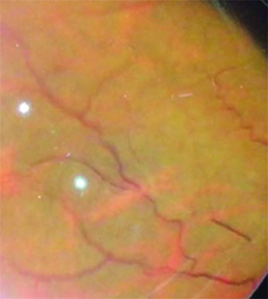

Fue derivada a oftalmología por presentar dificultad en la visión, descripta como ¨falta de visión periférica¨, alteración compatible con escotoma temporal superior en ambos ojos (AO). Al examen de fondo de ojos se observan vasos exangües, arrosariamiento venoso y vasculitis temporal inferior en AO (Imágenes 3, 4, 5 y 6). Se realiza campo visual sólo de ojo derecho (Imagen 7), por incapacidad de la paciente para completar el examen del ojo izquierdo debido a la dificultad motora que presenta. Se puede observar un escotoma relativo superior. En la retinofluoresceinografía (RFG) se localiza un área de hiperfluorescencia perivascular, en tiempos medios compatible con vasculitis periférica de AO (Imágenes 8 y 9) y con la alteración visual descripta por la paciente.

Imágenes 3 y 4: FO, OD y OI respectivamente, retinas aplicadas 360°, papilas excavación fisiológica de bordes netos, brillo macular acorde a la edad.

Imágenes 5 y 6:

se evidencia, arrosariamiento venoso, vasos exangües y vasculitis en terminación de la arcada temporal inferior.